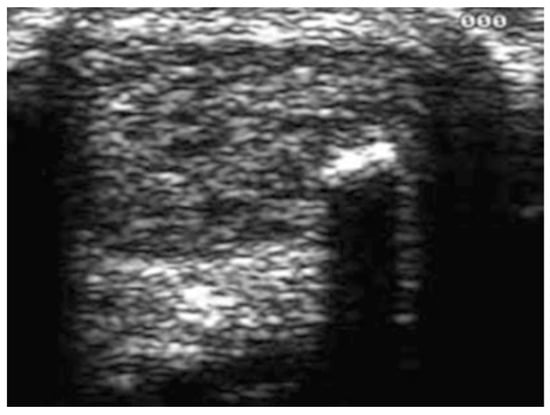

Conservative AT treatments lack strong evidence support, and affected patients have an increased risk of long-term morbidity with undefined clinical outcomes [22]. Diagnostic imaging, such as plain radiography, ultrasounds (US) (Figure 1) and magnetic resonance imaging (MRI), can be required to verify or to exclude a clinical suspicion [23].

Figure 1.

Ultrasonographic appearance of Achilles tendinopathy in a 28-year-old male soccer player at presentation. The longitudinal scan shows that the tendinopathic tendon is thicker than the asymptomatic contralateral one. The normal, well-ordered fibril distribution is lost.